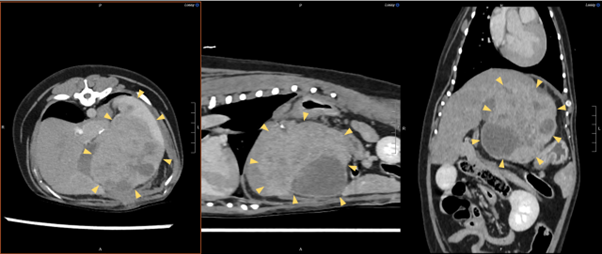

Diagnostic imaging is important for tumour localisation, assessment of morphology, staging and surgical planning, and in some cases may allow prediction of histological diagnosis.

Abdominal ultrasound (US) allows confirmation of the presence of a hepatic mass and aids morphological classification. Surgical planning can be performed based on US in smaller well-demarcated tumours but may not be as reliable in larger tumours, where it can be more challenging to assess mass interaction with adjacent structures such as the caudal vena cava. Triphasic CT (Figure 1) is often superior to US at assessing liver tumours as it allows detection of smaller lesions and can more accurately assess the relationship between large masses and adjacent soft tissue structures. In some studies, imaging features have also been used to differentiate benign from malignant tumours and even specific histological types (Griebie et al., 2017; Kutara et al., 2014). Visualisation of the tumour arterial supply is also essential for planning interventional treatments such as chemoembolisation. Thoracic imaging via either three-view radiographs or CT should be performed to screen for metastasis and complete staging in cases of malignant hepatic tumours.